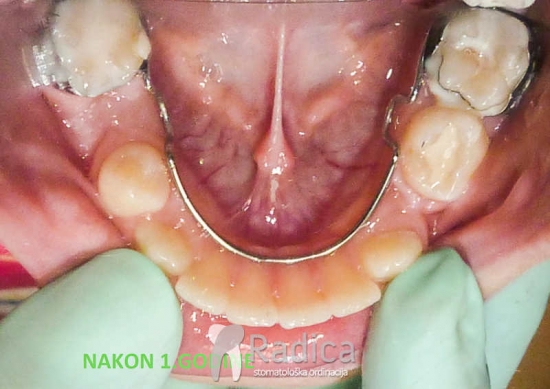

Primjeri korištenja lingvalnih i transpalatinalnih lukova:

1. Prerani gubitak mliječnih molara. Lingvalnim lukom spriječavamo pomak trajnih molara naprijed.

2. Impakcija mliječnog drugog molara – mliječne” petice” i trajnog drugog premolara (trajne “petica”):

3. Transpalatinalni lukovi za pojačanje “sidrišta”: